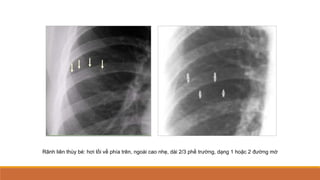

Rãnh liên thùy bé: hơi lồi về phía trên, ngoài cao nhẹ, dài 2/3 phế trường, dạng 1 hoặc 2 đường mờ

Rãnh liên thùybé: hơi lồi về phía trên, ngoài cao nhẹ, dài 2/3 phế trường, dạng 1 hoặc 2 đường mờ